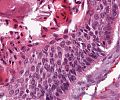

A70 Adenokarzinom des Kolon

Tumordrüsen mit deutlicher Kernpleomorphie

A70 Adenokarzinom des Kolon

Klein- und großdrüsige Tumordifferenzierung an der Invasionsfront